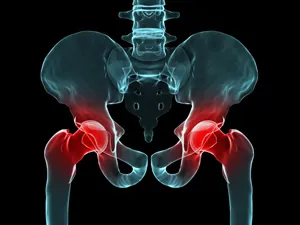

골반 부위에 통증이 나타나면 흔히 "파"로 알려진 "절뚝거림"으로 이어지는 경우가 많습니다. 고관절 통증은 크게 세 가지 방향으로 나뉩니다: ▲서혜부(사타구니) ▲측면 ▲후면으로, 각각의 방향에 따라 의심되는 질환이 달라집니다. 그중 가장 많이 보고되는 증상은 사타구니 통증입니다.

고관절 발달 이형성증이나 대퇴골두 충돌 증후군이 있을 경우, 대퇴골두의 무혈성 괴사가 말초 골절로 확장되면 사타구니 부위에 통증이 발생하는 것이 보통입니다. 고관절 외측의 통증은 주변 연부 조직의 손상 또는 염증으로 인한 대전자 통증 증후군(GTPS)과 관련이 있으며, 고관절 후방 통증은 주변 근육의 긴장이나 비대로 인해 이상근 증후군이 좌골 신경을 압박하는 상황에서 발생할 수 있습니다.